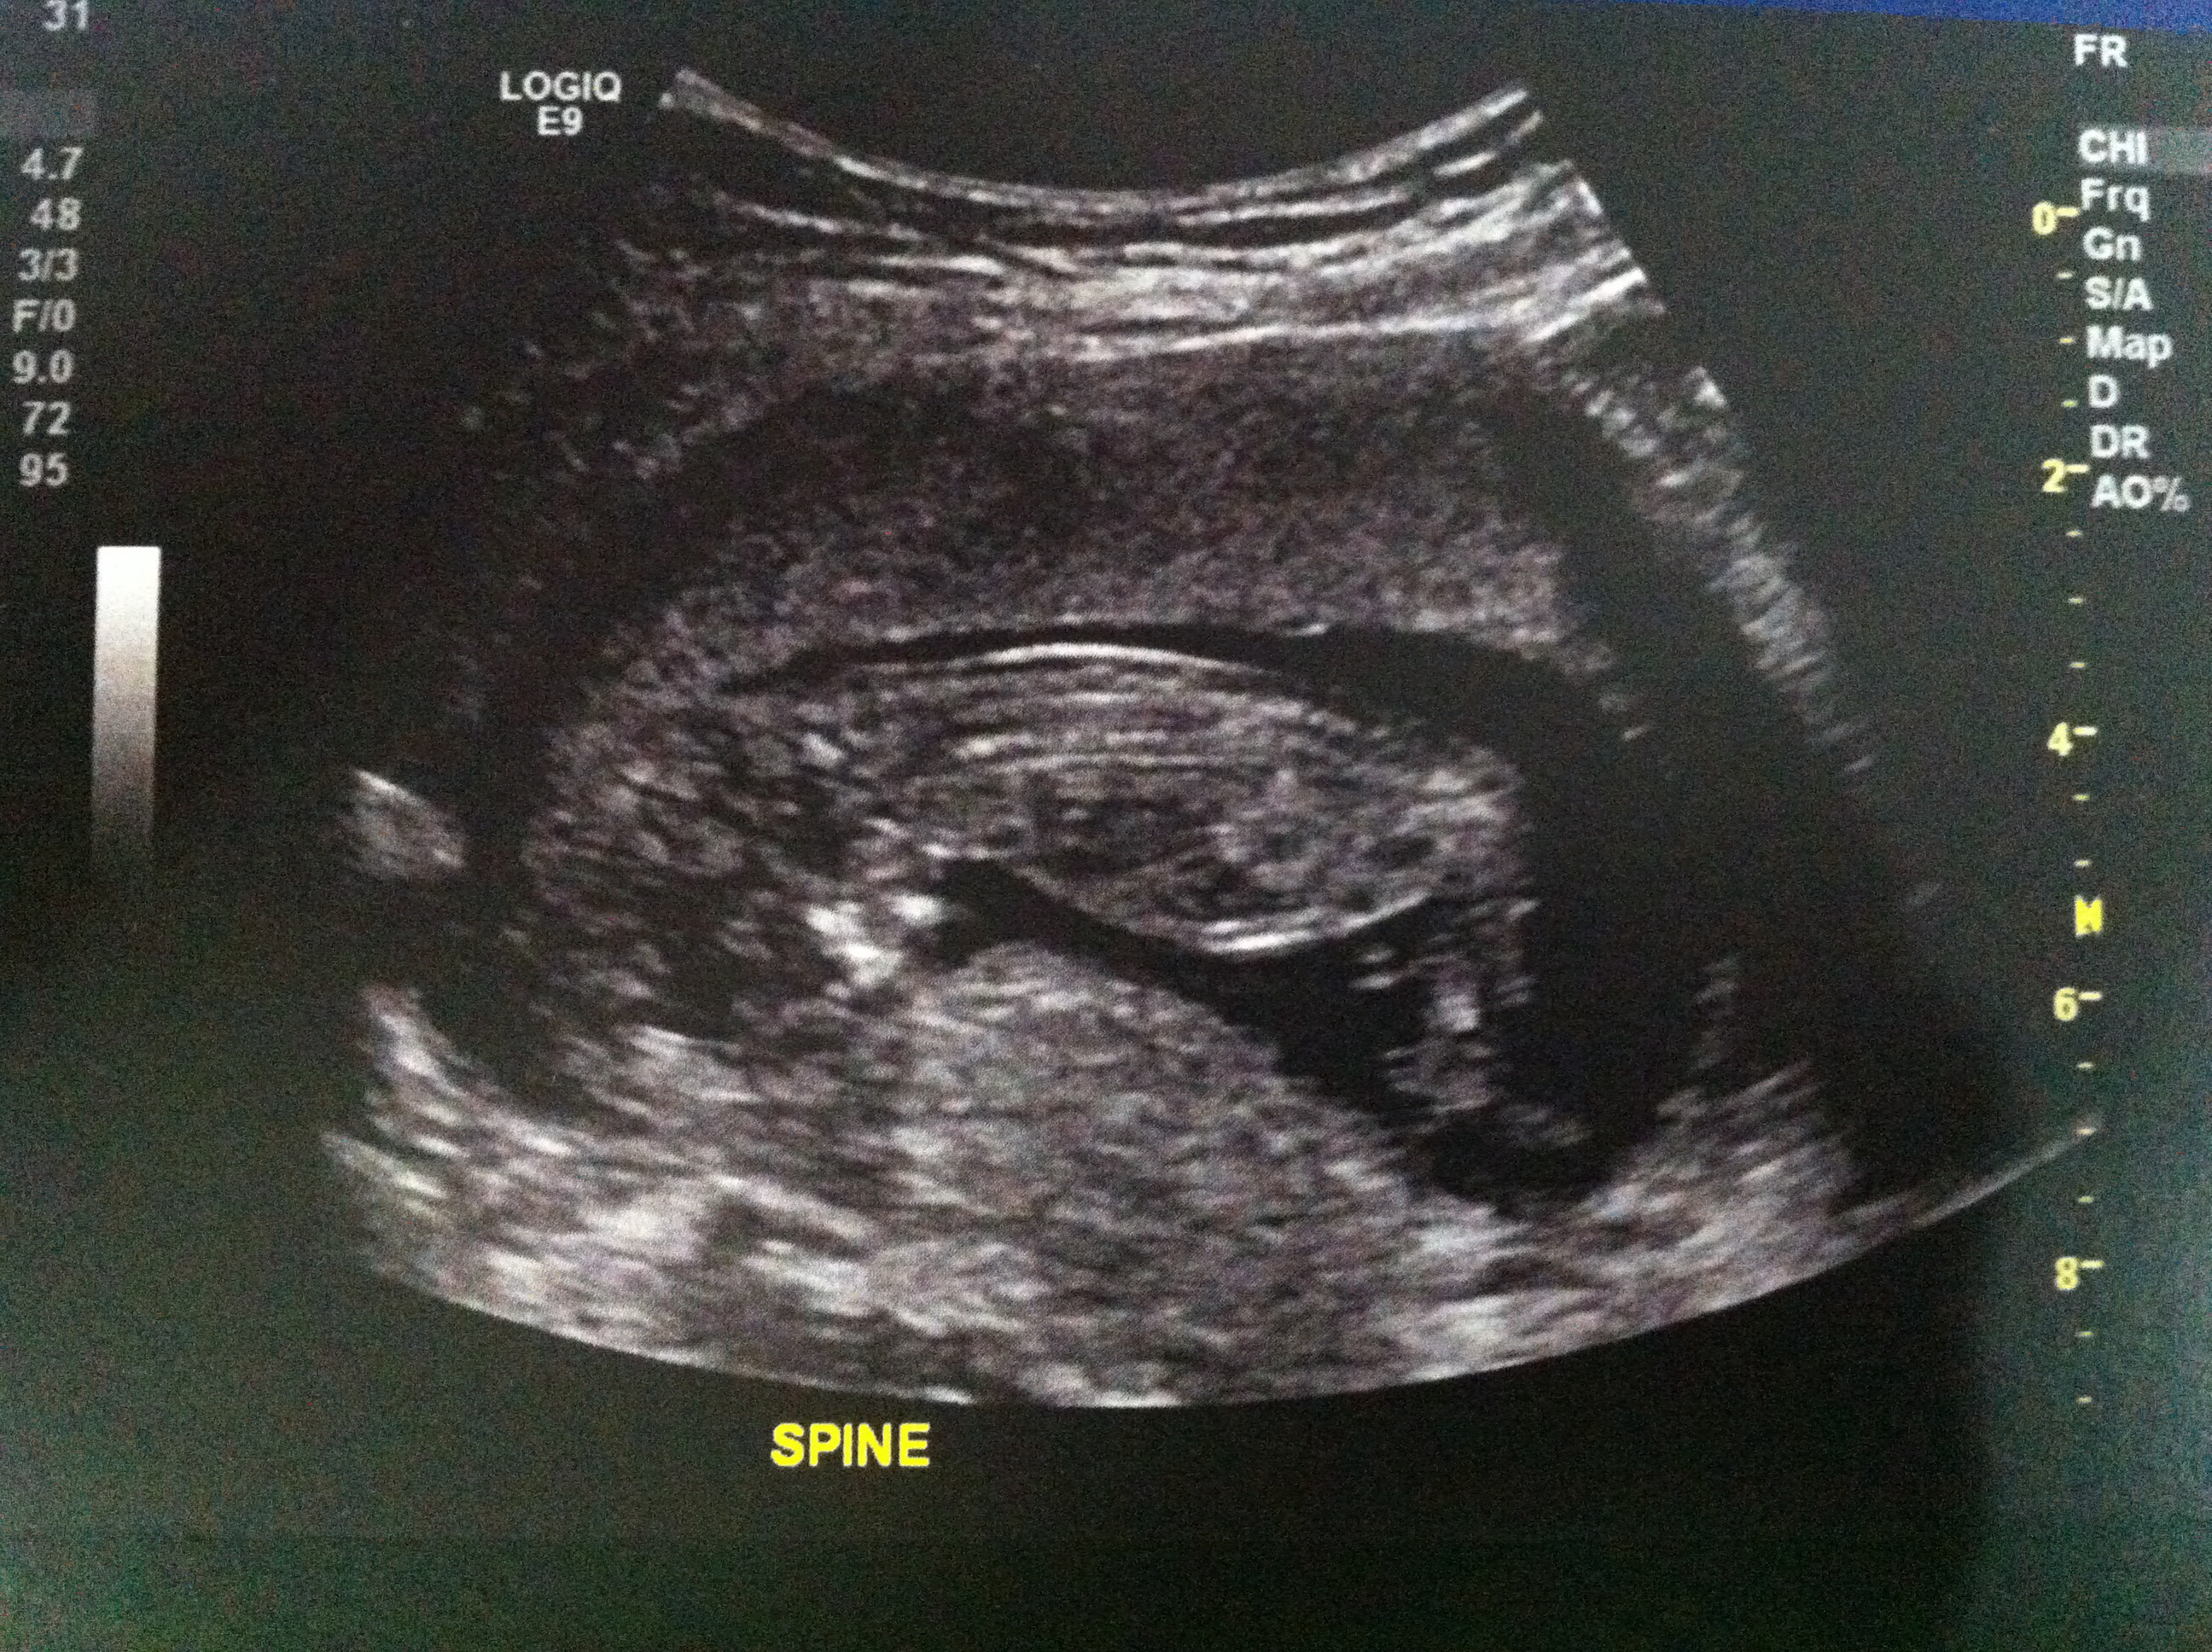

13+1w NT Ultrasound

Hi all! I had my NT sca today and the lady was very unhelpful. When I asked if she knew about the nub theory she went on a big thing about how she didn't believe in it and afterwards whenever she would go anywhere near the nub shot, she would move over or away very quickly so I never got a chance to check it out myself. Quite disappointing but oh well.

I still thought I would give it a go posting here see if anyone can see something I can't otherwise anyone care to guess on skull theory? Attachment 23469Attachment 23470

I can't see any nub. But the skull looks flat at the brow which may indicate boy. Congrats on baby :)

I think I maybe see a very girly nub.

I think I see that girly nub, too

Girl lean based on the newer ones. Cant be 100% though because of the movement. Doesn't believe in nub theory but makes sure to avoid it... Gotta love people like that! Hopefully if you have any more between now and the 20ish week anatomy scan you get someone more helpful!

Slight girl lean but really hard to tell!!

Ditto girly lean more based on seeing pics of other girls at this gestation than guessing off any nub! X

Brow and frontal lobe look boy, nub looks more girly but could be on the rise.

55/45 boy.

I don't see a nub, but boyish skull. GL!